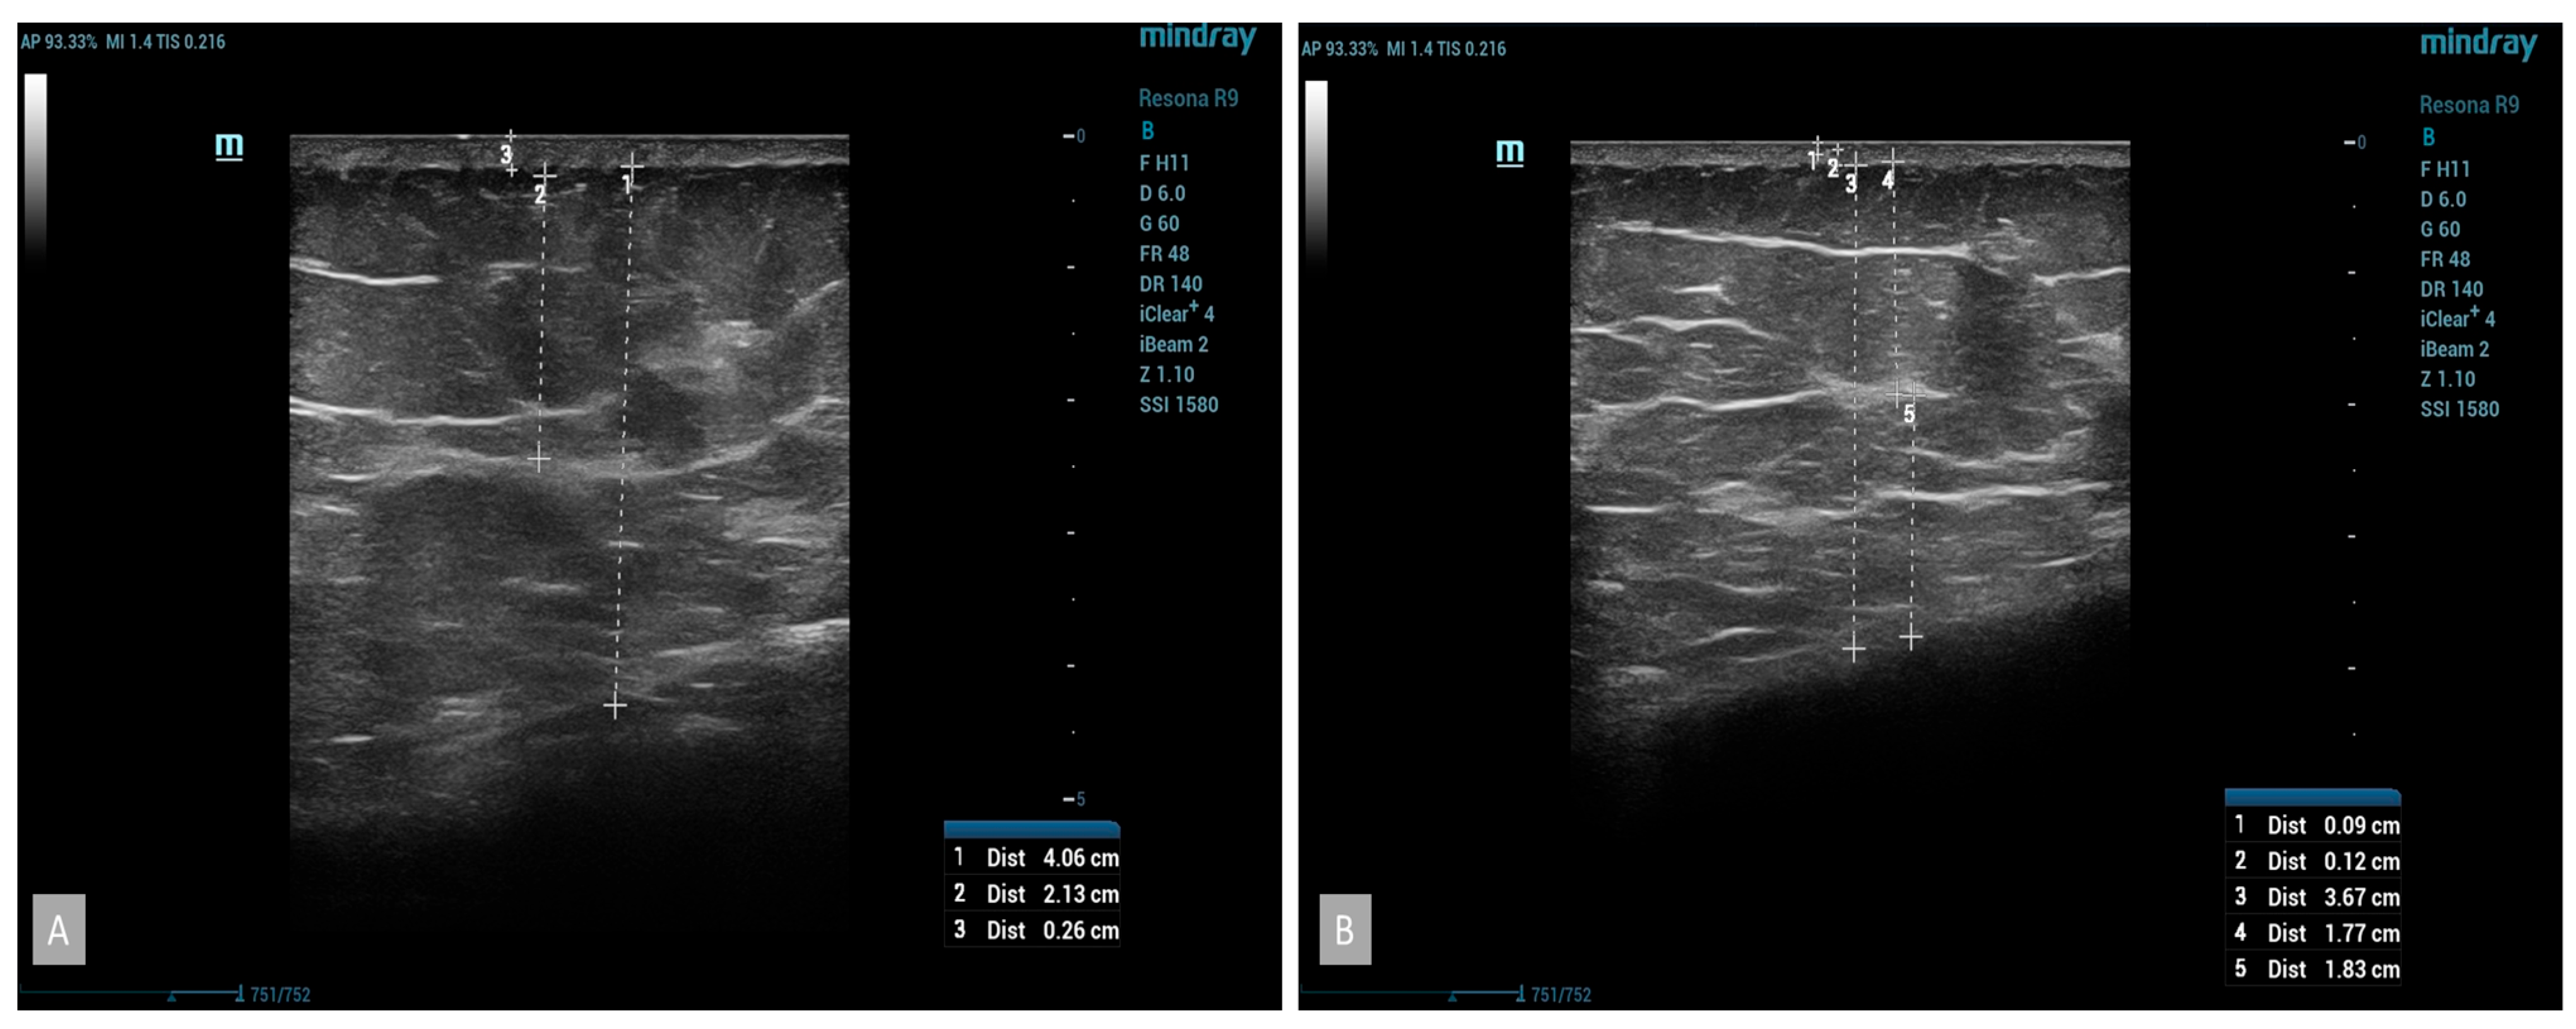

B-mode ultrasound examinations revealed significant changes in the parameters studied. The thickness of the subcutaneous tissue was reduced, confirmed by the results obtained from measuring the circumference of the thigh (Figure 4). The average reduction in the thickness of the subcutaneous tissue in the group using cellulite cream was 2 mm after 42 days and 3 mm after 84 days of treatment. No statistically significant changes were noticed in the placebo group (Figure 5). The analysis of the thickness of the dermis showed that, following the anti-cellulite treatment used, no substantial changes were found. Similarly to the case of the thickness of the subcutaneous tissue, no significant differences were noted in women taking the placebo. As for the thickness of the epidermis after the completion of treatment, no differences were observed in both the hypertonic cream group and the placebo group before and after the completion of treatment. The comparison of echogenicity before and after anti-cellulite treatment showed an improvement in subcutaneous tissue echogenicity in 25% of the patients with hypertonic cream according to the index of reduction of edema of subcutaneous tissue. In the placebo group, the echogenicity did not change. In addition, the analysis of vascular-connective shoots showed that in cases of moderate–severe cellulite (grade II or III according to the Nürnberger–Müller scale), the latter showed an irregular and discontinuous trend, and after the application of the device, there was an improvement in the regularity of the same in 20% of the hypertonic cream group. No significant differences were noted in women taking the placebo. The additional color-doppler US examination showed that 53% of patients showed abnormalities in the venous system of the lower limbs, particularly regarding the presence of perforating veins such as Cockett B in 25% of patients, Boyd in 15% of patients, and Huxley in 1% of patients.

Figure 4. At baseline US, subcutaneous thickness with fibro-tissues bands was evident (A); after treatment, reduction in subcutaneous thickness and an increase in the echogenicity of the hypodermis were evident (B).